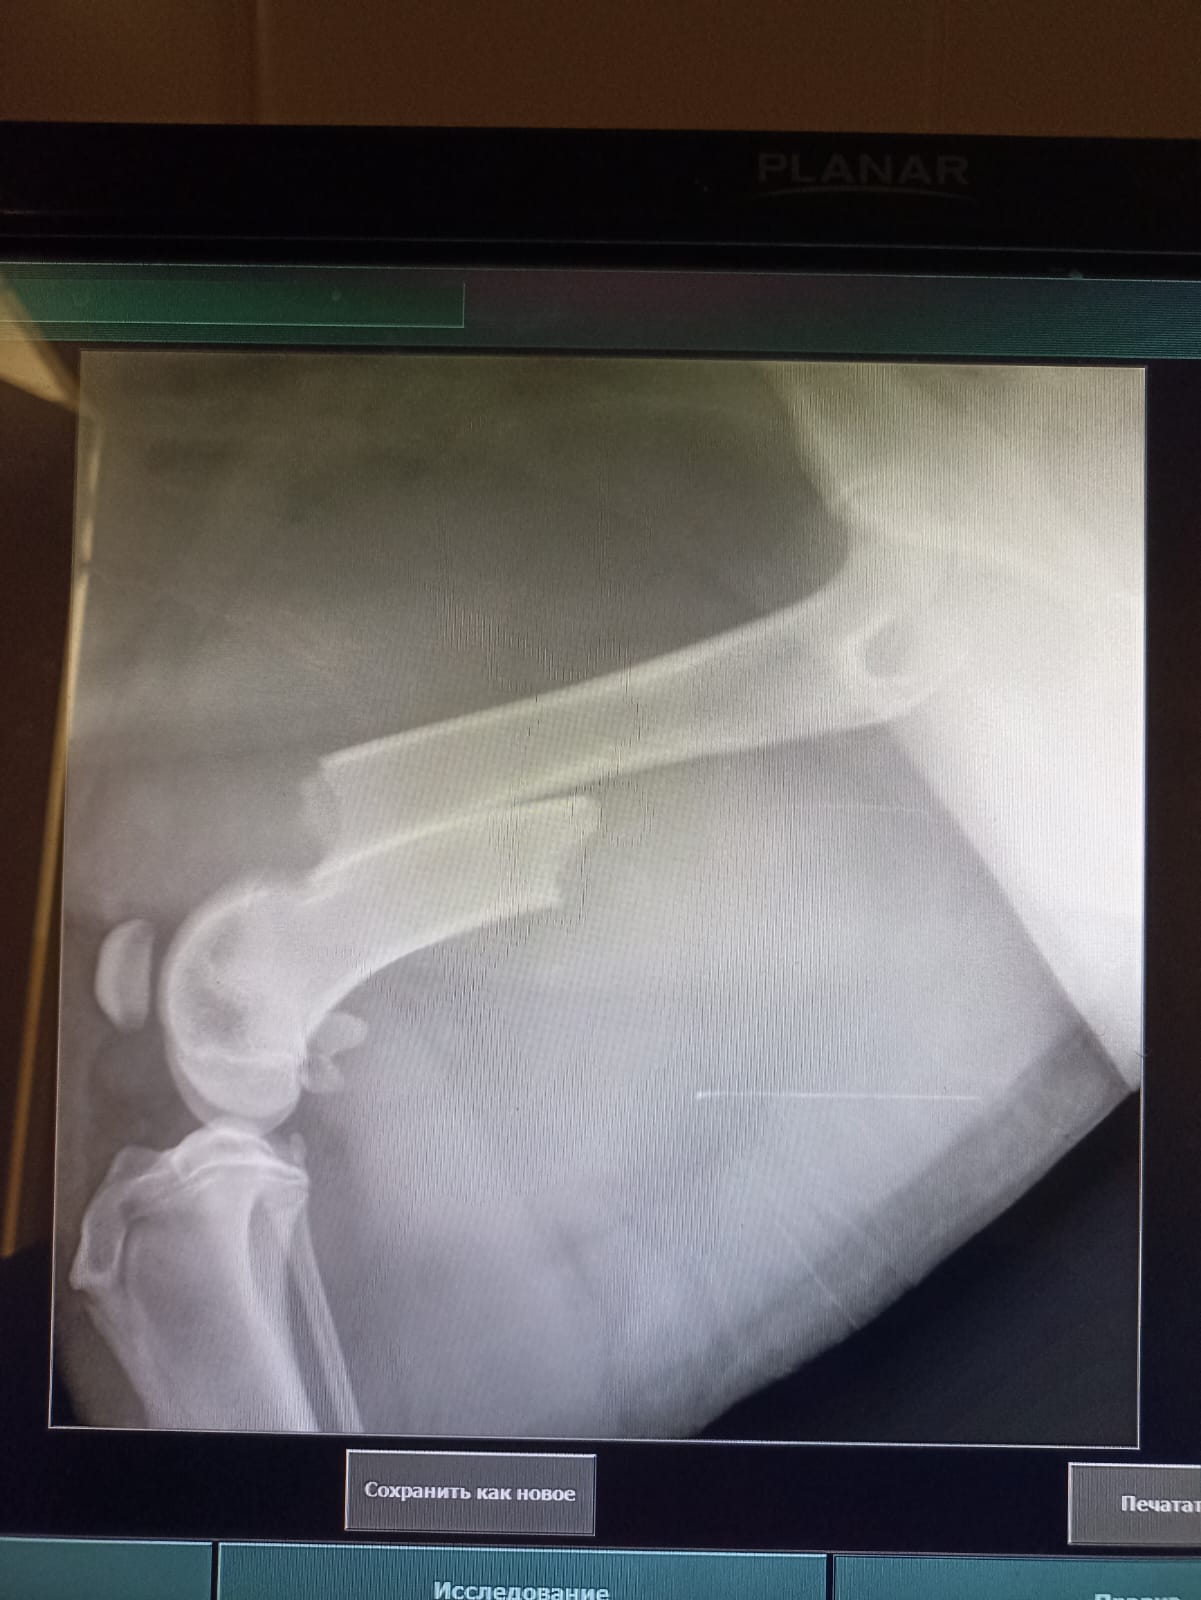

Волонтёр привела молодую суку ризена со сломанной лапой в клинику к Насте pani Stasi. Вроде перелом не сильно свежий.

Ногу будет хирург смотреть и может в ближайшее время прооперируют.

Её забрала заводчица. И что-то там у них случилось, то ли лошадь понесла, то ли что, в общем, собака перепрыгивала через телегу и сломала лапу. У заводчицы тоже ключица сломана, может ещё что-то.

Ветеринар позвонила знакомому волонтёру, говорит, чего усыплять, я её соберу, рентген только надо.

Операцию сделали, собрали лапу на две пластины. Выписка попозже будет.

Да, задняя правая сломана.